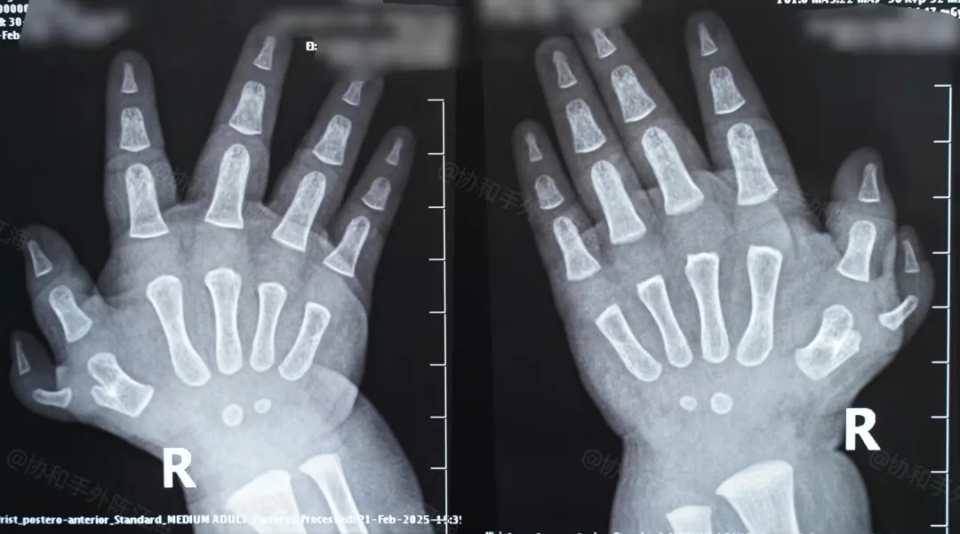

多指│案例55《没有遗传,孕期也没有乱吃东西,为什么我的宝宝会多一个指头?》

宝宝一出生,家人还来不及喜悦,就发现了宝宝右手多了一个拇指,这对家长来说是不能接受的,孩子妈妈努力回想自己怀孕的细节:

就像是这个宝宝的多指,其实情况还是比较复杂的,宝宝右手拇指的关节囊很松,如果不做处理,将来可能还会影响到活动,所以在手术的时候,会对尺侧副韧带进行加强,整个手术主要是去除多指,然后对关节囊进行修补,其余部分都比较常规。